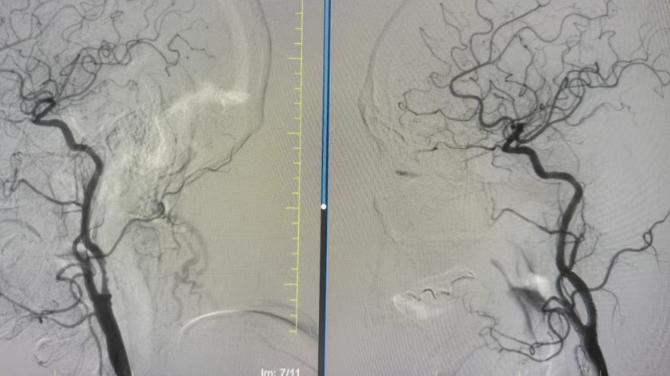

尽管方大爷年事已高,但手术的获益远大于风险。在医护团队详细告知病情、手术流程及风险后,方大爷及家属果断决定接受血管内介入治疗。完善术前准备后,手术在局部麻醉下顺利开展,介入团队凭借精湛的技术,精准定位血管狭窄部位,平稳将支架送入并成功释放,狭窄血管被顺利撑开,充沛的血流重新顺畅灌注大脑,为方大爷的生命中枢“续航”。